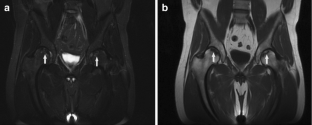

Incidental findings other than scoliosis were recorded in 104/247 (42%) patients, most often affecting the musculoskeletal system (65/247 patients, 26%). We found 16/247 (6.5%) significant incidental findings likely to affect clinical management, including avascular necrosis of bone in eight patients (five with NF2), eight insufficiency fractures, and four non-neurogenic neoplasms (Hodgkin's lymphoma, liposarcoma, dermoid cyst, large uterine myoma requiring excision). Scoliosis was seen in 50/247 patients (20%), including 8/55 with NF2 (15%) and 11/51 with schwannomatosis (22%).

Incidental findings in the neurofibromatoses frequently involve the skeleton. Given the relatively high incidence of unsuspected osteonecrosis and stress fractures, close attention to the skeleton on WBMRI is advised. In addition, knowledge of common incidental findings can help clinicians prepare patients who undergo WBMRI for potential unexpected findings.